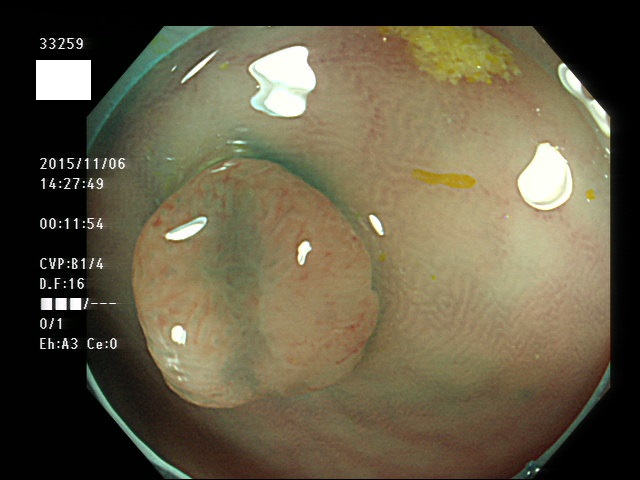

上記100名より抽出した平坦・陥凹型腺腫(=癌化の危険が高いが見落としやすい病変)の内視鏡写真